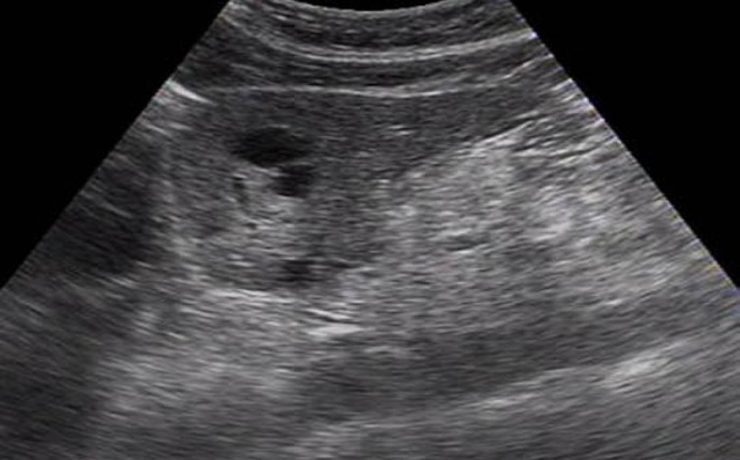

Fibroadenoma de tejido mamario ectópico axilar

Es el tumor benigno más común de la glándula mamaria de mujeres jóvenes. A pesar de que un 95% de las mujeres existe tejido mamario en la axila (cola de mama) y de que incluso en 6 de cada 100 es clínicamente evidente. Los reportes de este tumor en la